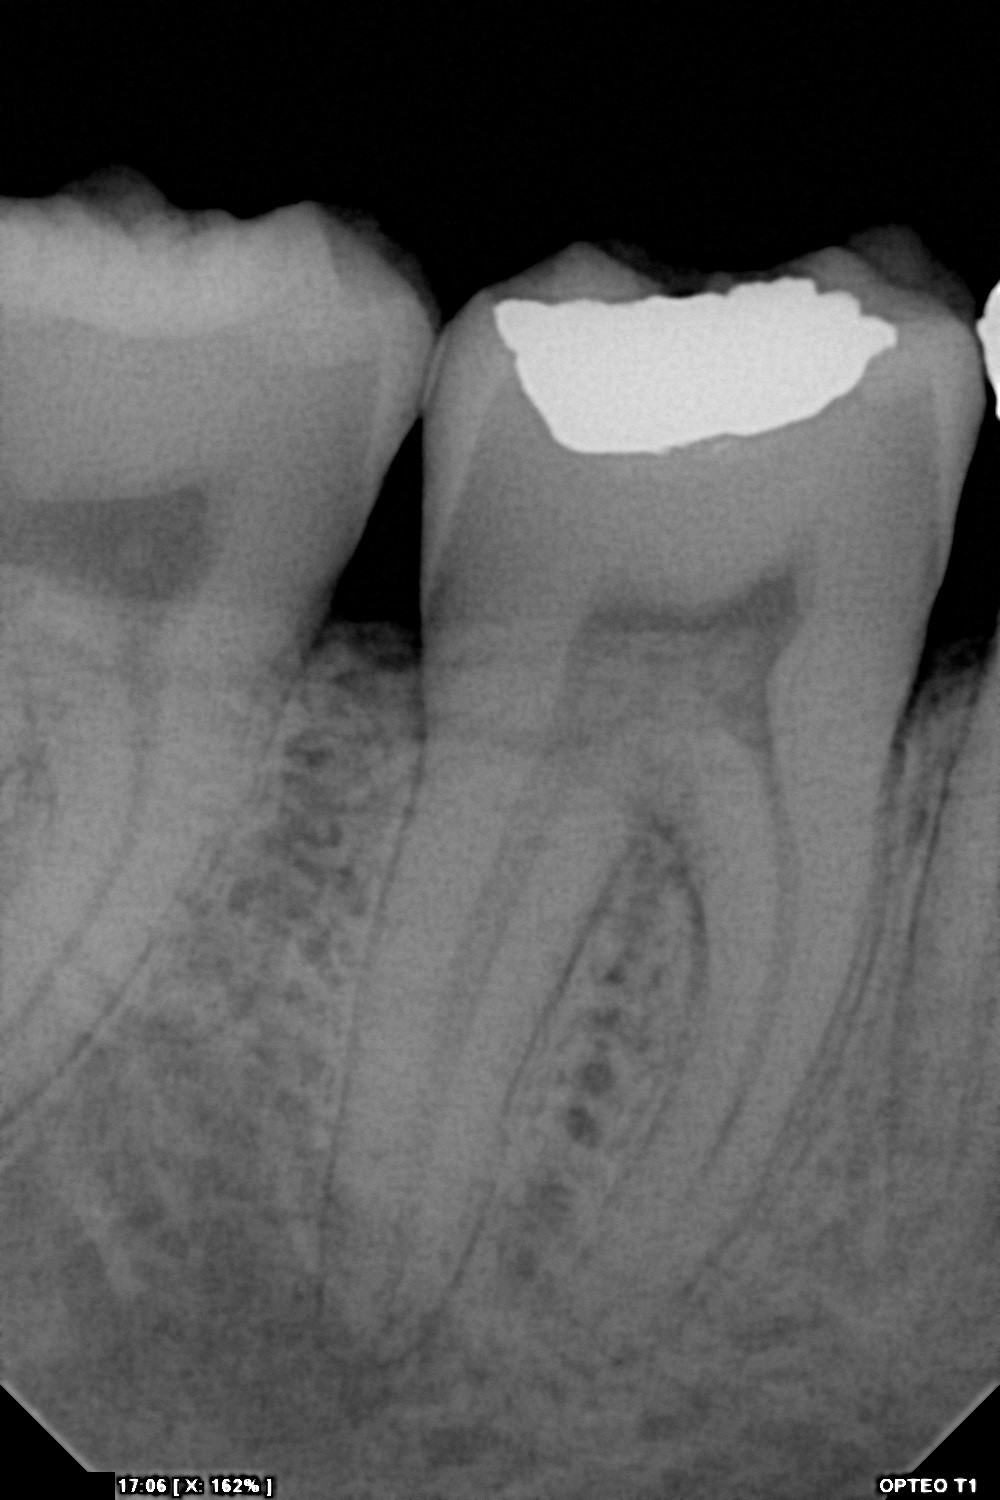

سنسور رادیوگرافی تک دندان مدل OPTEO

سنسور رادیوگرافی دیجیتال دندان مدل Opteo

سنسور ديجيتال راديوگرافي دندان مدل Opteo T1

سنسور پنج لایه و 14 بیتی با قدرت تفکیک بیش از 16000 رنگ در حد فاصل سیاه و سفید

Full HD sensor - CMOS sensor 26.3 lp/mm

Grey levels: 14 bits - 16384 grey levels

600mm² Sensitive surface Direct USB - without box